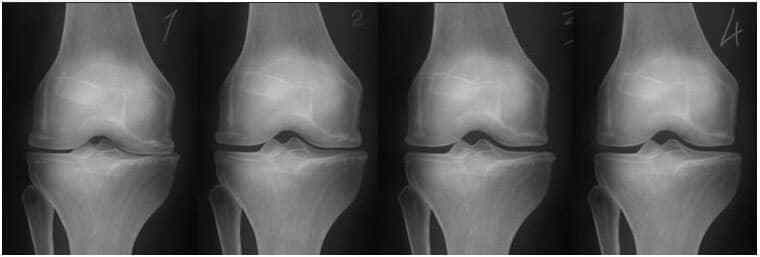

На зображенні нижче показана типова картина відновлення колінного суглоба.

Суглоби знімок